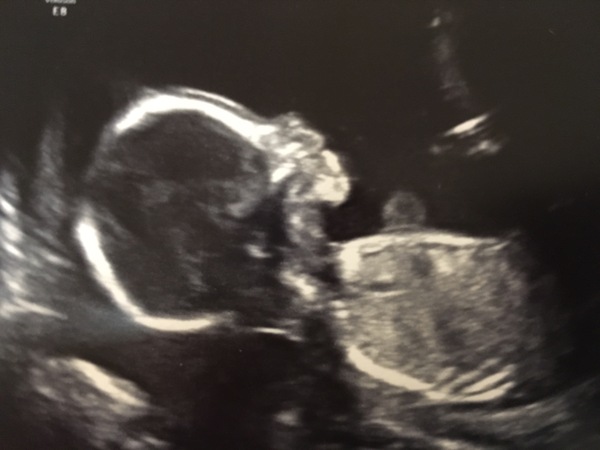

Thankyou ladies! Proud to say ITS A BOY💙💙no mistaking with that willy lol

August 2018 #4